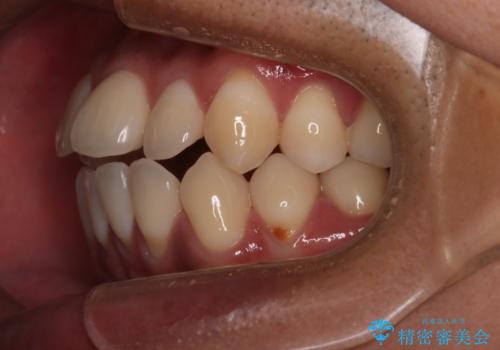

- 全体的に歯並びをよくしたいとのことで来院されました。初診時、患者様はセラミック矯正とワイヤー矯正で迷われていました。

開口(オープンバイト)のため噛み合わせを考慮してワイヤー矯正を提案させていただきました。

IPR(歯と歯の間を削る処置)と顎間ゴムを行い歯並びを整える治療計画を立てました。

早く終わらせたいとの事でしたが、ゴム掛けを頑張っていただいたので

9ヶ月という短い期間で治療が完了しました。

矯正後は保定経過とメンテナンスで経過を見ていきます。